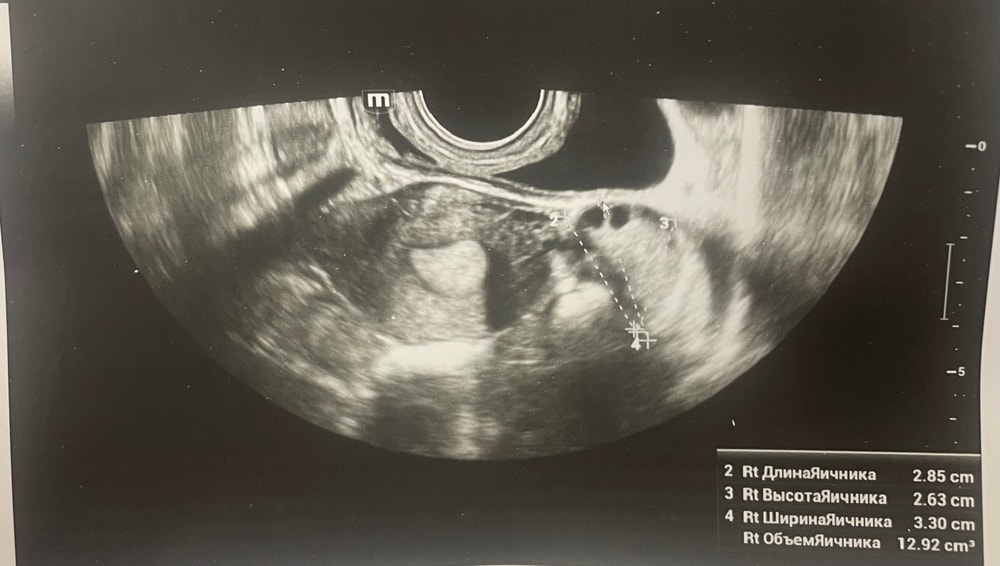

Ждем дня Х/тесты/признаки БДобрый день, мы с мужем планируем беременность и в этом месяце произошло что то странное… дата начала последней менструации 4 октября закончилась 8, овуляцию отслеживала всю неделю почти сначала были бледные еле заметные полоски, 23 октября жирные четкие полоски, 24 октября стала чуть бледнее но яркая, вообщем положительный ещё был, с 25 числа тест уже отрицательный, через день после овуляции 26 числа стала странно себя чувствовать и во время овуляции болел живот то справа то с лева и поясница, так через день после начали болеть соски грудь вообще не болела, живот то болит то нет и с поясницей также, позже появилась небольшая изжога, нога немеет правая не знаю с чем связано), все это началось за 2 недели до месячных в середине цикла скажем так 29 числа пошла на узи спустя 6 дней грубо говоря гиня сказала что у меня была очень хорошая овуляция, что её признаки сохраняются до сих пор так скажем, желтое тело СПРАВО 20 мм, мои симптомы и все это очень похоже на беременность сказали большая вероятность, я очень была рада и надеялась, после узи появились выделения с комочками, до этого были просто густые белые выделения, утром тоже самое, пошла опять к гинекологу она сказала это может быть при ранец беременности сказала какие свечи купить, вечером я попала в не большое ДТП, удар был в поясницу и копчик, живот начал тянуть и поясница сильно болеть, начала болеть сама грудь помимо сосков, живот прошел относительно быстро, а вот поясница ломит до сих пор, решила сходить ещё раз на узи очень испугалась, на узи я пошла 31 через два дня после предыдущего и уже к другому гинекологу, моя на больничном, она сказала, что у меня отсутствуют даже косвенные признаки беременности и желтое тело с ЛЕВО А НЕ С ПРАВО, я не понимаю как такое может быть, очень расстроилась и совсем забыла про фото узи, она мне его не дала только заключение и как выяснилось уже не дадут оно не сохранилось, сказали переделывать, я очень доверяю своему гинекологу, но по заключению второго врача о беременности не может быть и речи в этом цикле, я не понимаю как желтое тело оказалось с лево если оно точно было справа в этом я уверена, а вторая врач уверяет во Братном, живот в обуляцию хоть и болел с двух сторон но больше справа помойму, вообщем я не понимаю есть ли шанс что я беременна или все таки нет, я понимаю что это слишком рано, до задержки ещё 4 дня, но мне плохо уже неделю по симптомам даже больше это же не просто так, я прикреплю фото заключения, могу ли я быть беременна, если посмотреть на эти заключения хотябы, подскажите пожалуйста фото узи относятся к 29.10, без фото 31.10